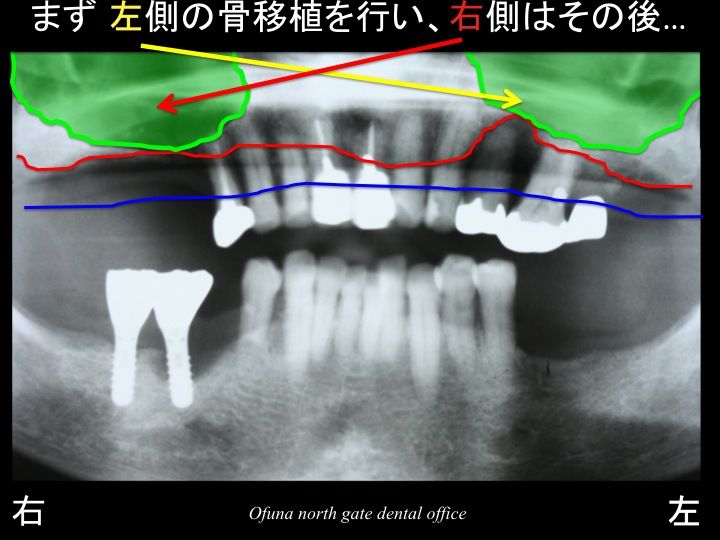

左右ともサイナスリフト法(上顎洞底挙上術) を行い、インプラント治療を行うことが最も良い方法です。

しかし、サイナスリフト法(上顎洞底挙上術) がどれほど大変であるのかが分からないため、まずは 左側を行い、その後に右側を行うかどうか決めたいとの患者様のご希望がありました。

次に骨の状態に問題のある上顎左側の奥歯です。

この部分には、サイナスリフト法(上顎洞底挙上術) を行い、2本のインプラントを埋入する計画を立てました。

次に上顎左側の奥歯に骨移植(上顎洞底挙上術) を行いました。

移植した骨が安定するまでには、かなりの期間がかかります。

約6ヶ月以上です。

そのため、もし 上顎左側の奥歯にインプラント治療を行うためには、

上顎洞内部に骨移植を行うことが必要になります。

この治療をサイナスリフト法(上顎洞底挙上術) と言います。